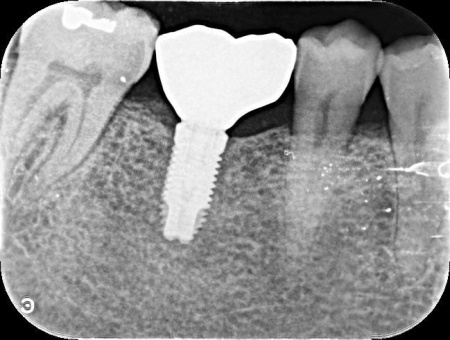

60代男性 歯が抜けている部位にインプラント治療を施した症例

拝見したところ、左下奥歯(第1大臼歯)が抜けており、見た目が気になるだけでなく奥歯でしっかりと噛むことが難しくなっていました。

その結果、十分な骨の量があり、噛み合わせの歯もインプラントを入れた際に自然に噛める位置に生えていたため、インプラント治療を行う条件は問題ないと判断しました。

①左下奥歯の欠損部位にインプラント埋入手術を実施。インプラントを正しい位置と角度であごの骨に埋入し、傷の治りを待つ

②インプラントがあごの骨に問題なく定着したことを確認したあと、インプラントの上に人工歯を装着する